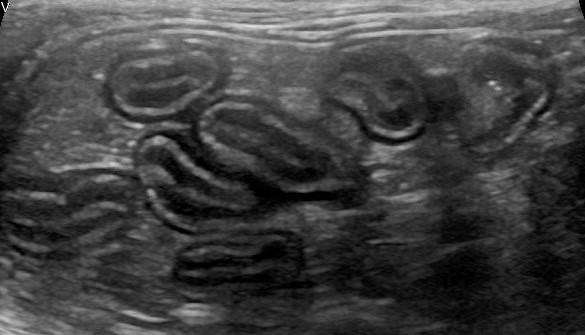

–Intestino: aumento de grosor de forma difusa afectando principalmente a capa muscular. Presencia de al menos dos zonas de engrosamiento severo (masas) con pérdida de estructura en capas.

En la ecografía abdominal a las 2 semanas de empezar la quimioterapia no se encontraron masas ni en riñón ni en intestino,

estando éste levemente engrosado de forma difusa a nivel de la capa muscular pero manteniendo en todo momento la estructura en capas.

Estos hallazgos ecográficos junto con la evolución del paciente eran signos claros de respuesta a la quimioterapia por parte del gato cuya enfermedad entró en fase de clara remisión.